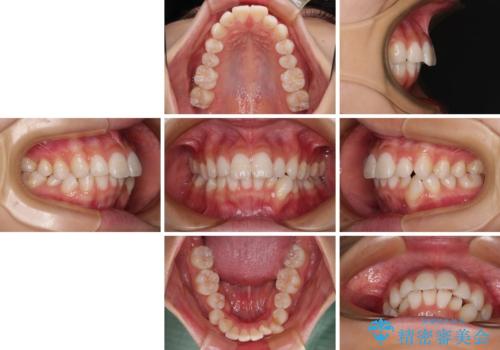

- 口を閉じたときに飛び出してしまう上顎前歯を気にして来院された患者様です。

下顎はデコボコが気になっていたため、上下左右第一小臼歯4本を抜去して、ワイヤー装置にて口元の突出感を改善するよう矯正治療を行うこととしました。

下唇に前歯が当たって跡が残ってしまう状態でしたが、スッキリとした口元に仕上げることができました。